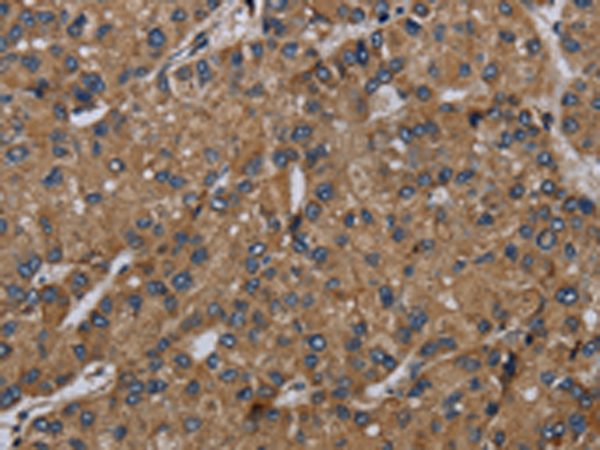

分类: 科研抗体货号: P08529别名: ZRF; MTF-1应用: IHC反应种属: Human